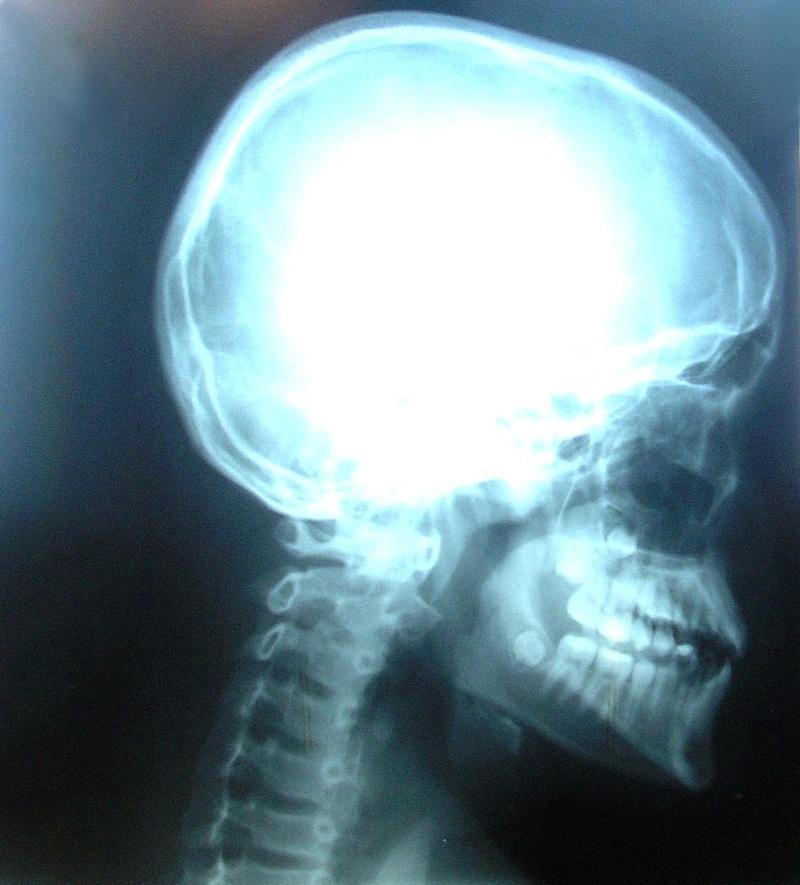

El tratamiento para esta osteofitosis consiste básicamente en analgésicos para el dolor, antiinflamatorios, reposo y terapia física. Solo en casos más graves se recurre a la cirugía. Esta condición debe ser diagnosticada por un médico, quien evaluará los síntomas, y según la edad y actividad del paciente, un estudio de rayos X, resonancias magnéticas o tomografías realizará el diagnóstico